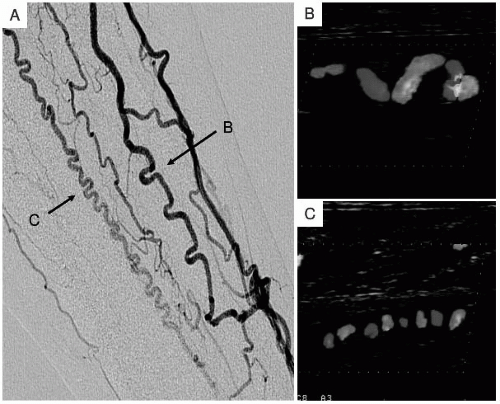

Treatment Of Thromboangiitis Obliterans (Buerger's Disease) With

obliterans thromboangiitis buerger disease angiography figure bosentan treatment